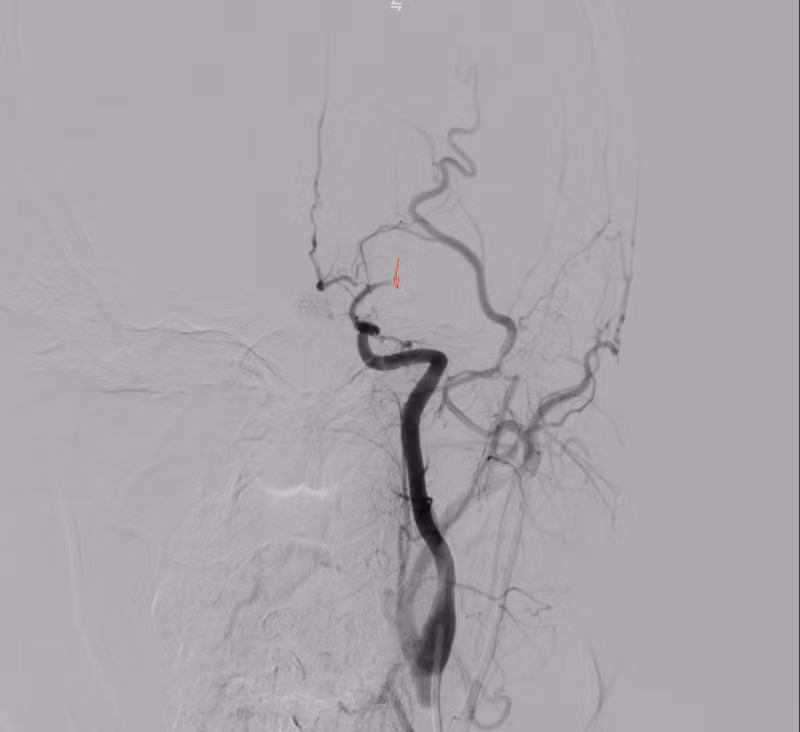

Kết quả chụp DSA xác định tắc động mạch não giữa trái đoạn M1 do hẹp nặng. Kíp can thiệp đã tiến hành nong bóng tái thông mạch máu, khôi phục dòng chảy lên não thành công.

dot-quy-nao-2.png

Hình ảnh: DSA trong can thiệp hẹp nặng M1

dot-quy-nao-3.png

Hình ảnh: Chụp DSA trước can thiệp thấy tắc M1 trái

dot-quy-nao-4.png

Hình ảnh: DSA sau can thiệp tái thông TICI 3